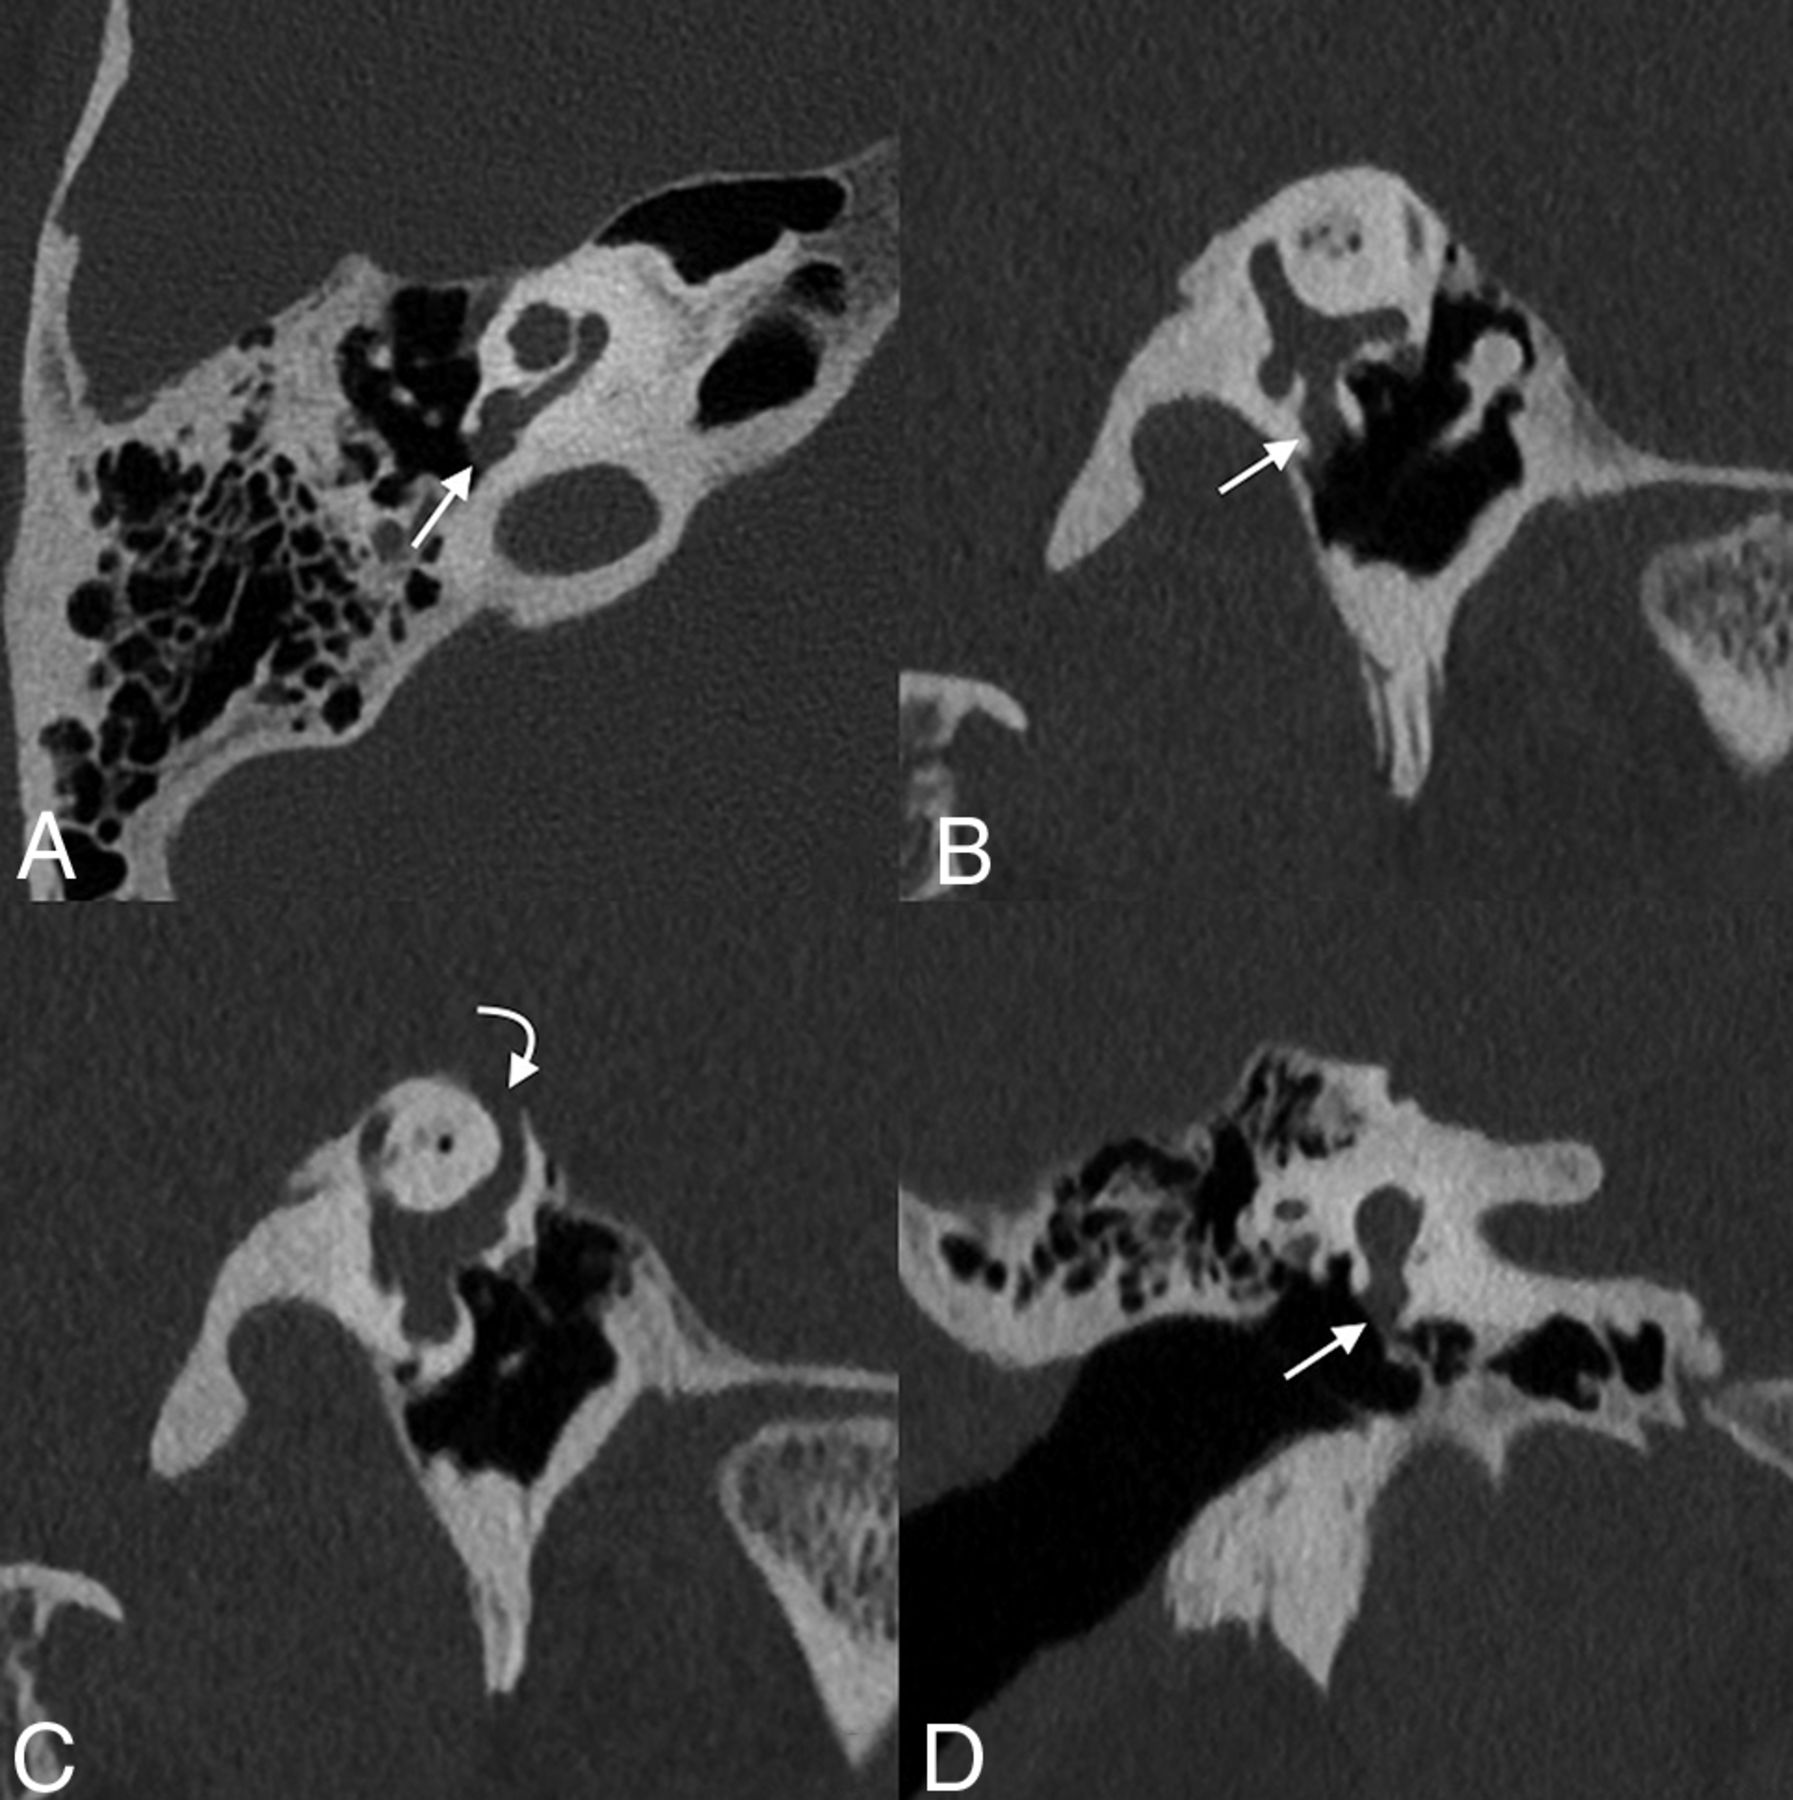

Labyrinthitis ossificans with round window involvement. Axial (A and B), Pöschl (C), and coronal (D) images of the left temporal bone of a 5-year-old with a history of prior tympanoplasty tube placements. Labyrinthitis ossificans is seen in the basal turn of the cochlea (straight arrows, A and D) with mineralization of the round window (curved arrows, B and C).

Otosclerosis with round window involvement. Axial (A), Pöschl (B), and coronal (C) images of the right temporal bone demonstrate bony changes compatible with otosclerosis adjacent to the round window, with marked narrowing of the round window niche (arrows).

Postoperative changes of round window niche occlusion for superior semicircular canal dehiscence. Axial (A), Pöschl (B and C), and coronal (D) images of the right temporal bone demonstrate a soft-tissue opacity corresponding to a mixed temporalis fascia and irradiated rib cartilage against the round window and within the adjacent niche (straight arrow). There is frank dehiscence of the superior semicircular canal (curved arrow).